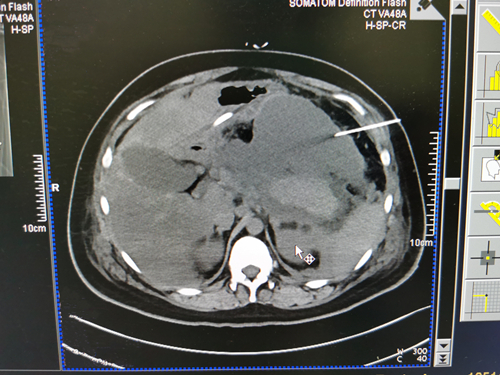

接到会诊,介入与血管外科王卫国主任、戴正行副主任仔细评估了患者病情,查看CT后发现患者腹腔存在多处包裹性积液,其中胰周积液为主。王卫国主任表示,虽然风险很大,但通过CT引导下进行精准穿刺,可大大降低风险,最终决定开展CT引导下穿刺置管引流。

在进行穿刺前行定位CT时,戴正行主任指导患者摆正体位。完成定位CT后,王卫国主任在预定位置进行局部麻醉,保留穿刺针,复查位置良好后,再换用穿刺针带负压沿引导位置穿刺进入积液区,抽出棕褐色坏死性积液,再次复查发现导丝到达预定位置,沿导丝置入猪尾型导管,接引流袋后可见引流液流出,最后复查CT见导管头位于胰头位置,引流通畅。左右侧腹腔积液均采用该方法穿刺引流,引流效果良好。